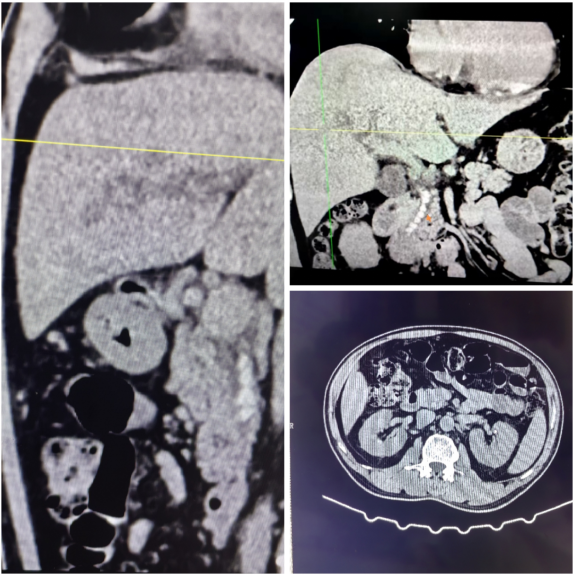

化脓性胆管炎+结石

患者因上腹剧痛、皮肤眼睛发黄入院, 经检查确诊为:感染性休克、急性化脓性胆管炎、梗阻性黄疸、胆总管结石、急性化脓性胆囊炎、糖尿病,病情危急! 化脓性胆管炎可不是小病——胆管里细菌疯狂繁殖,胆汁淤堵成“毒窝”,会引发感染性休克、肝衰竭、多器官衰竭,甚至猝死! 幸好及时就医,做了腹腔镜胆囊切除术、胆总管切开术、胆道镜取石术、T管引流术、腹腔引流术的微创手术。